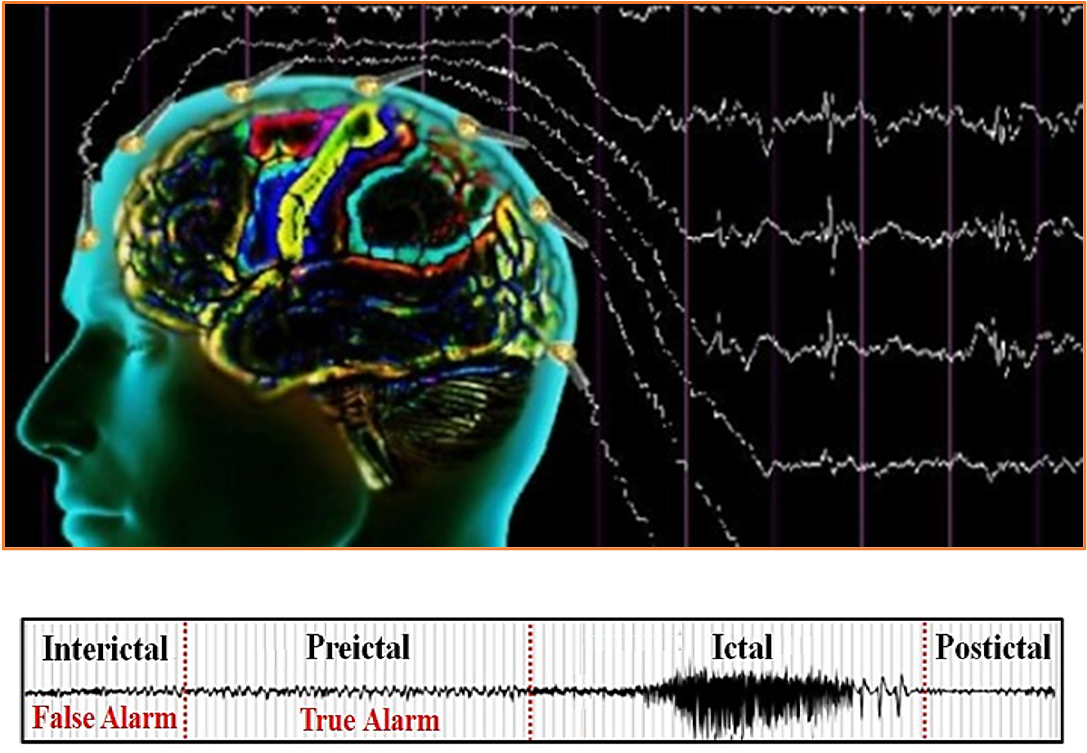

AI has also shown promise in brain tumor classification. Using three-dimensional convolutional neural networks, researchers can distinguish between high-grade and low-grade gliomas by extracting detailed spatial features from volumetric MRI scans. This approach helps clinicians design more effective treatment strategies.

Figure 3 Proposed approach for glioma brain tumor classification (Mzoughi 2020).